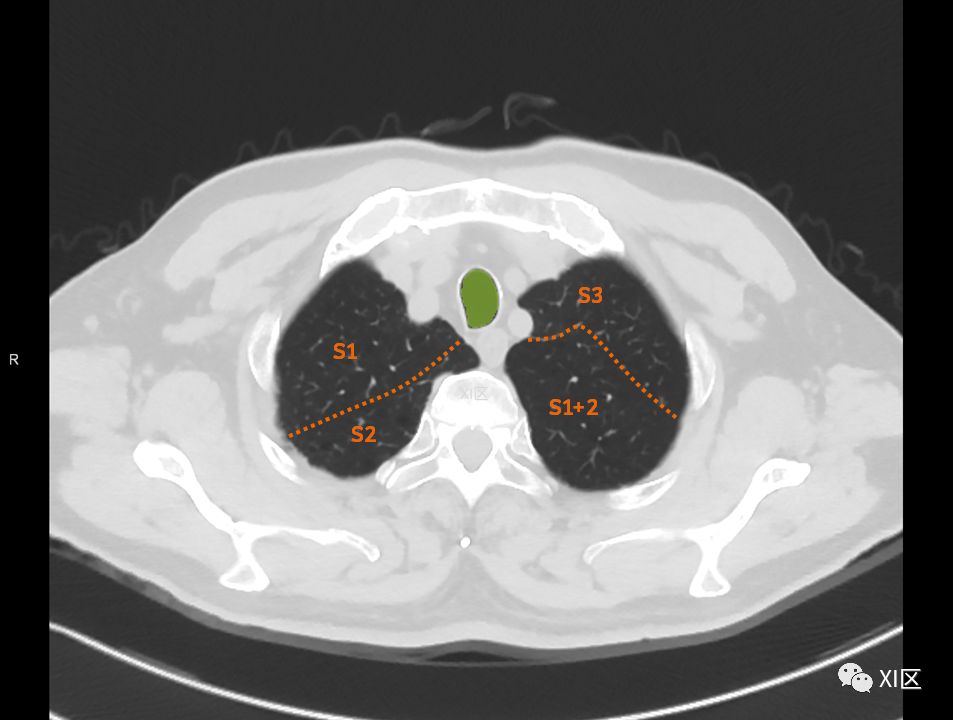

肺段划分-胸部ct断层影像-肺窗(七) 解剖图片

图片尺寸1080x810

肺段划分-胸部ct断层影像-肺窗(六) 解剖图片